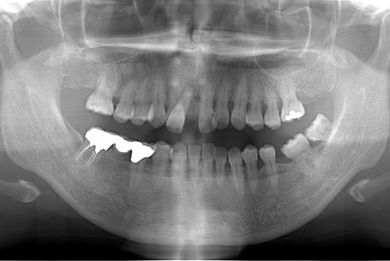

| 性別/年齢 | 女性 / 52歳 | ||||||||||||||||||||||||||||||||

| 主訴 | 歯周病で歯の位置がずれてしまった。 | ||||||||||||||||||||||||||||||||

| 治療内容 | インプラント2本(抜歯即日スピードインプラント)、メタルボンドセラミッククラウン4本 | ||||||||||||||||||||||||||||||||